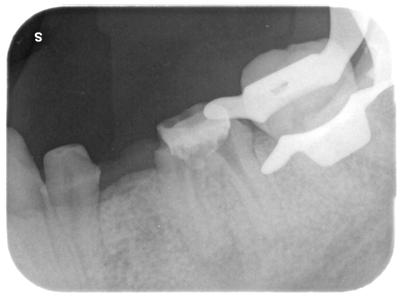

術前レントゲン写真。

セラミックの適合精度は極めて悪い。

ダメになるのは時間の問題。

近心根混尖に影がある。